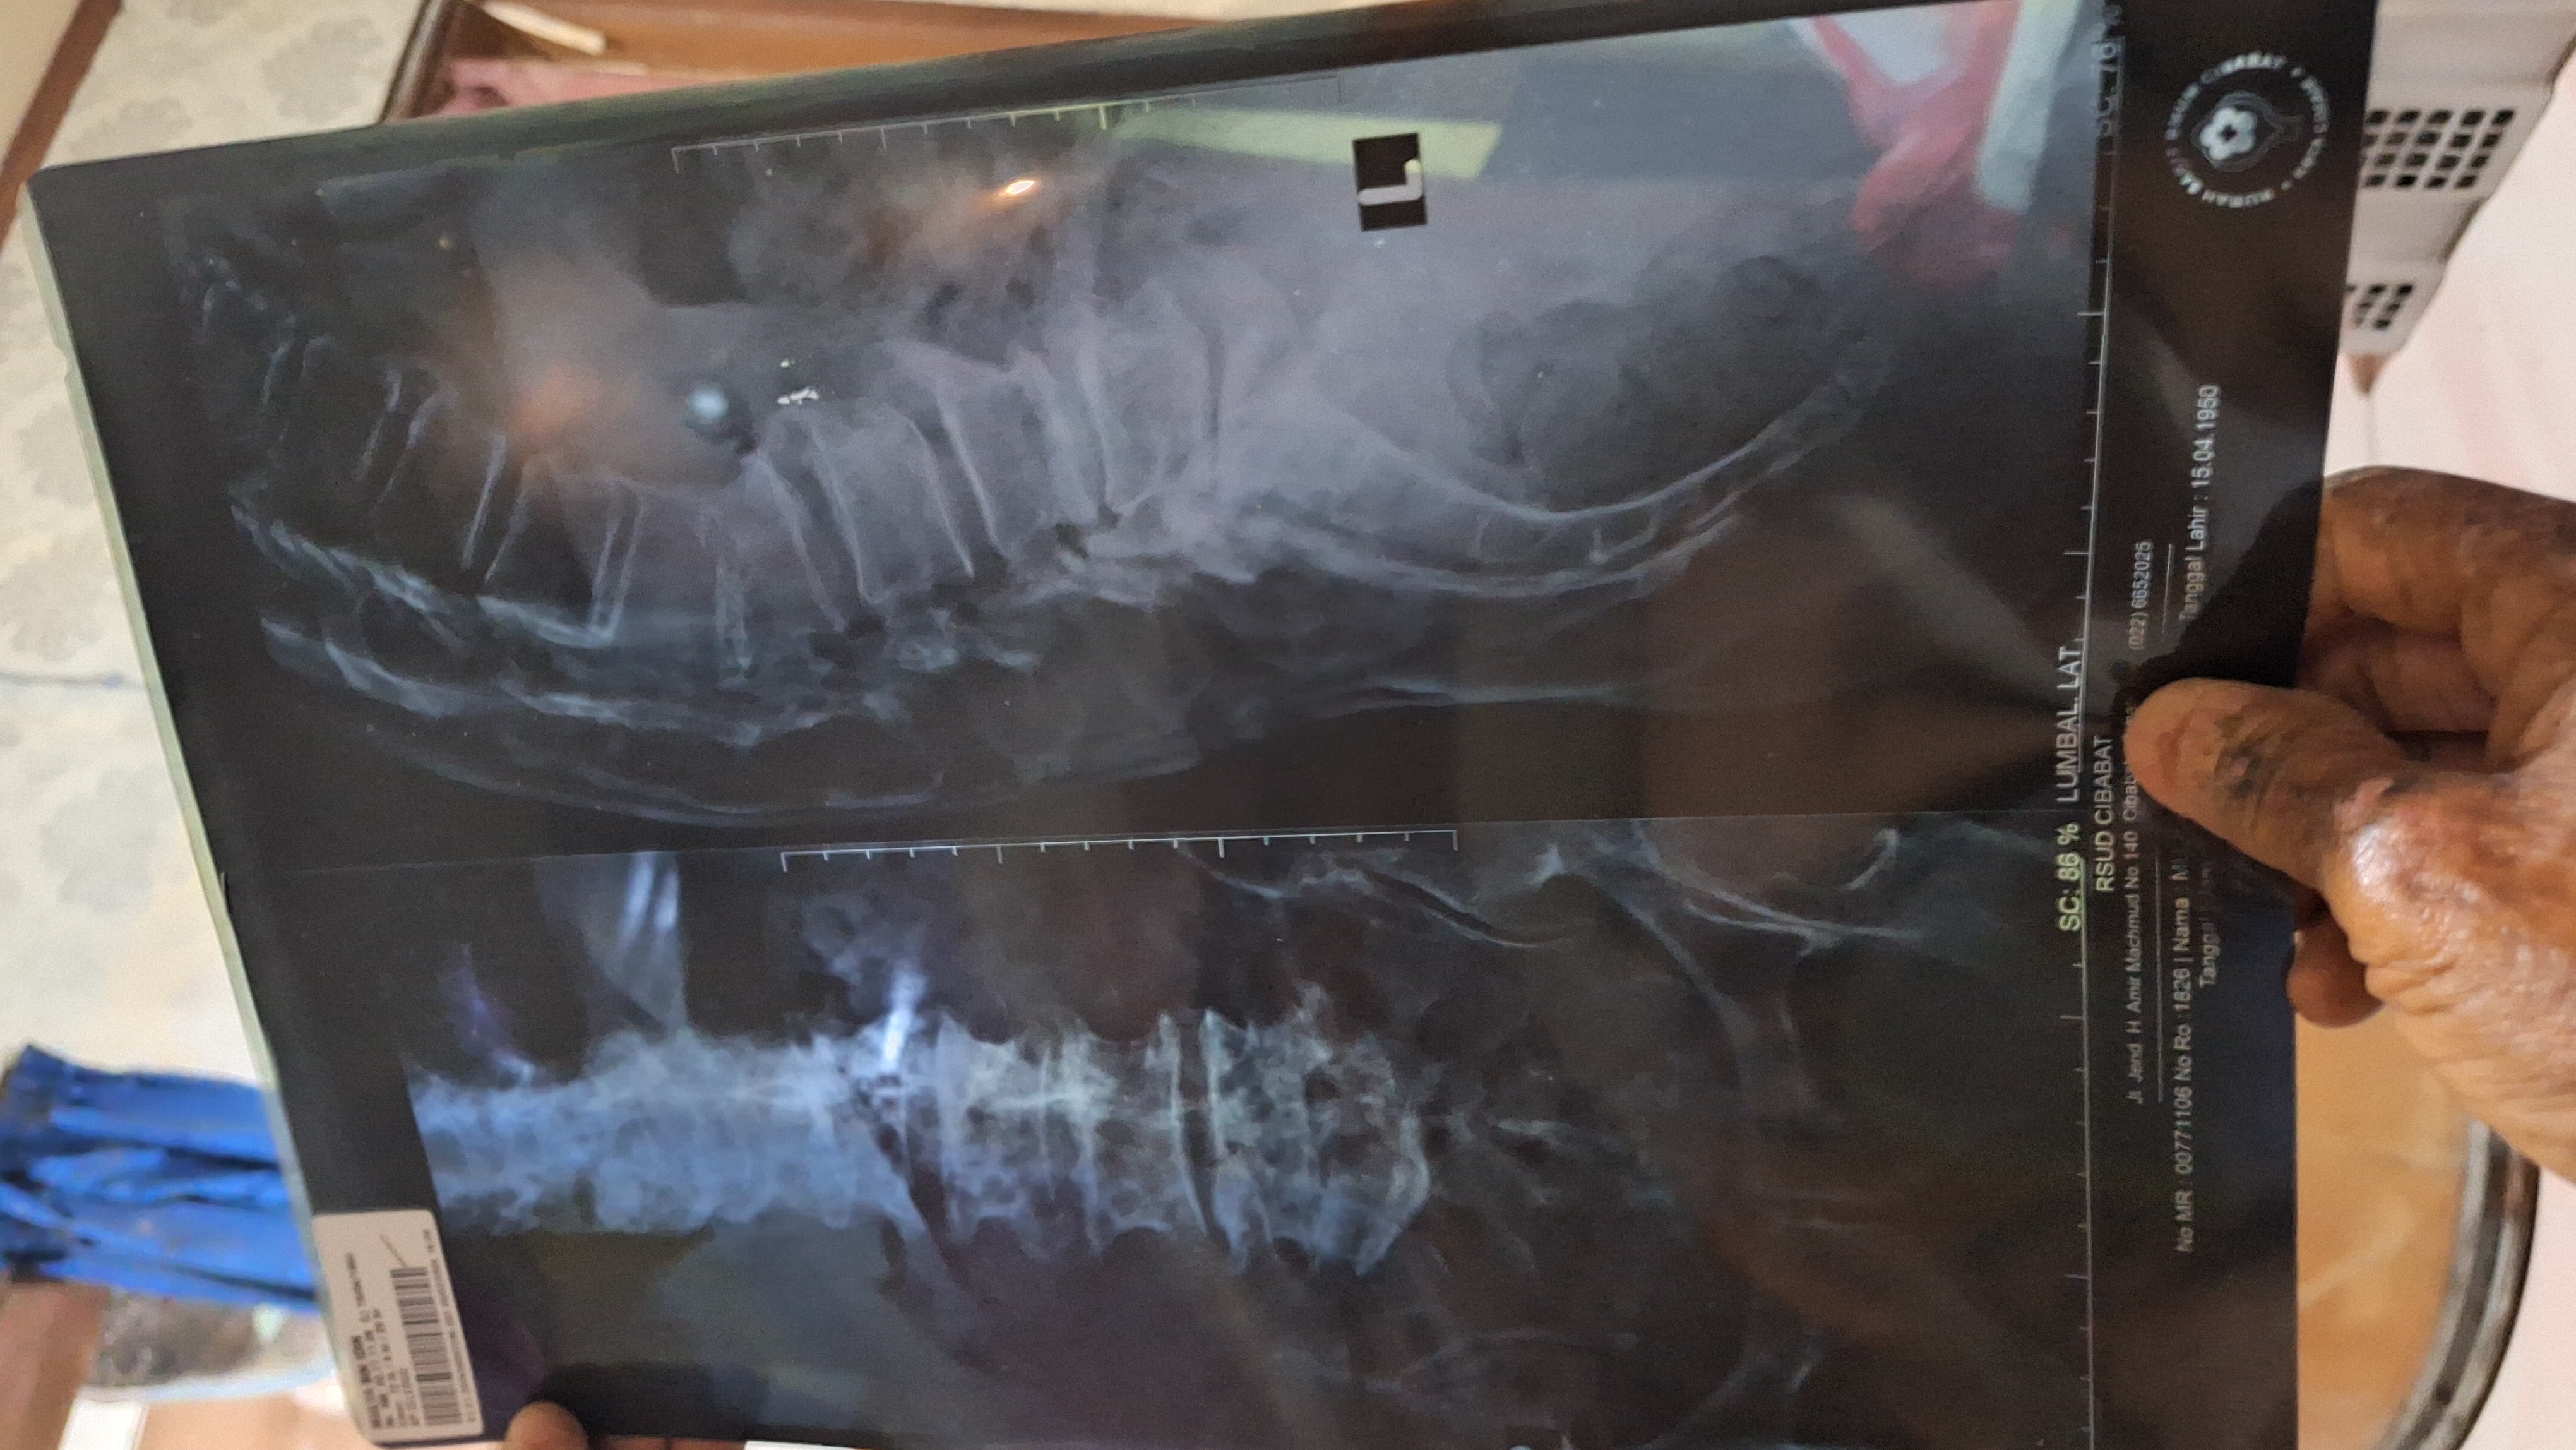

Kondisi Abah jauh dari kata sehat, tulang punggung Abah patah bikin tubuhnya bungkuk sampe kesakitan dan Abah di diagnosis mengidap Pneumonia yang menyebabkan paru-paru abah terisi cairan dan nanah.